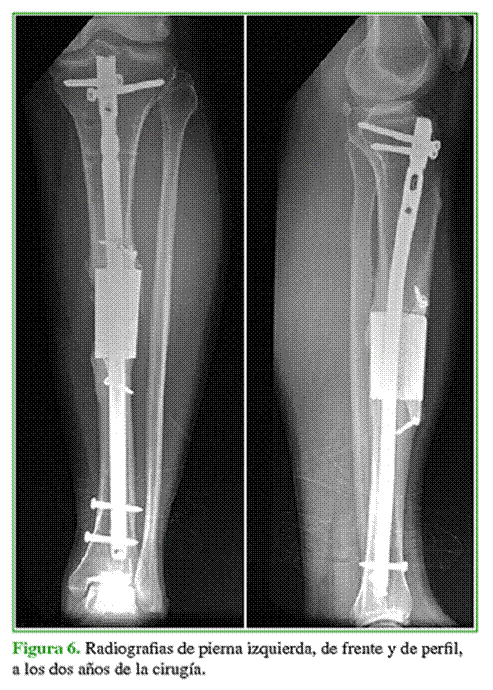

Dos semanas después se procedió a la osteosíntesis del antebrazo derecho más enclavado con antibiótico en la tibia izquierda. Al concluir el tratamiento antibiótico, se efectuó una biopsia por punción, todas las muestras fueron negativas y se procedió a la reconstrucción esquelética (Figura 6).